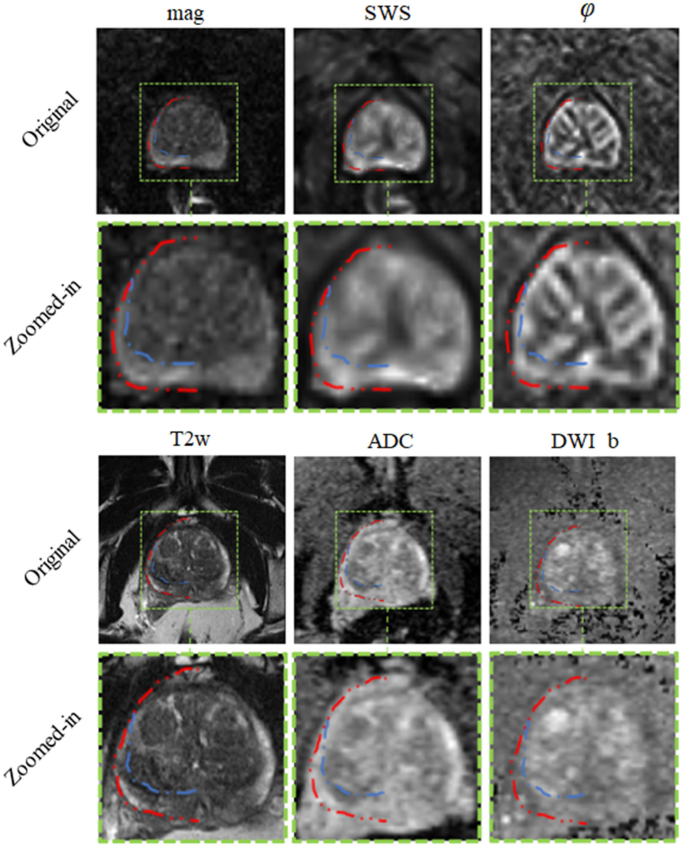

Our results show that IMs performed excellent across all maps and sequences with high values for DS and low values for HD. In our experiments, segmentation was most reliable when we used T2w and MRE magnitude images, which provide sufficiently rich anatomical details for automated prostate segmentation while quantitative parameter maps such as SWS, \(\varphi\) and ADC lack those details. Figure 9 depicts a variety of maps in a patient demonstrating that anatomy of prostate boundaries is well preserved on T2w and MRE magnitude images while it is less clearly visible on ADC, DWI_b, SWS and \(\varphi\) maps.

Different maps of the same patient. Second and forth rows show zoomed-in images of the first and third rows, respectively. Dotted red and blue lines highlight part of the segmentation for prostate and PZ, respectively and the rest of the delineation was omitted to show the actual pixel intensities.